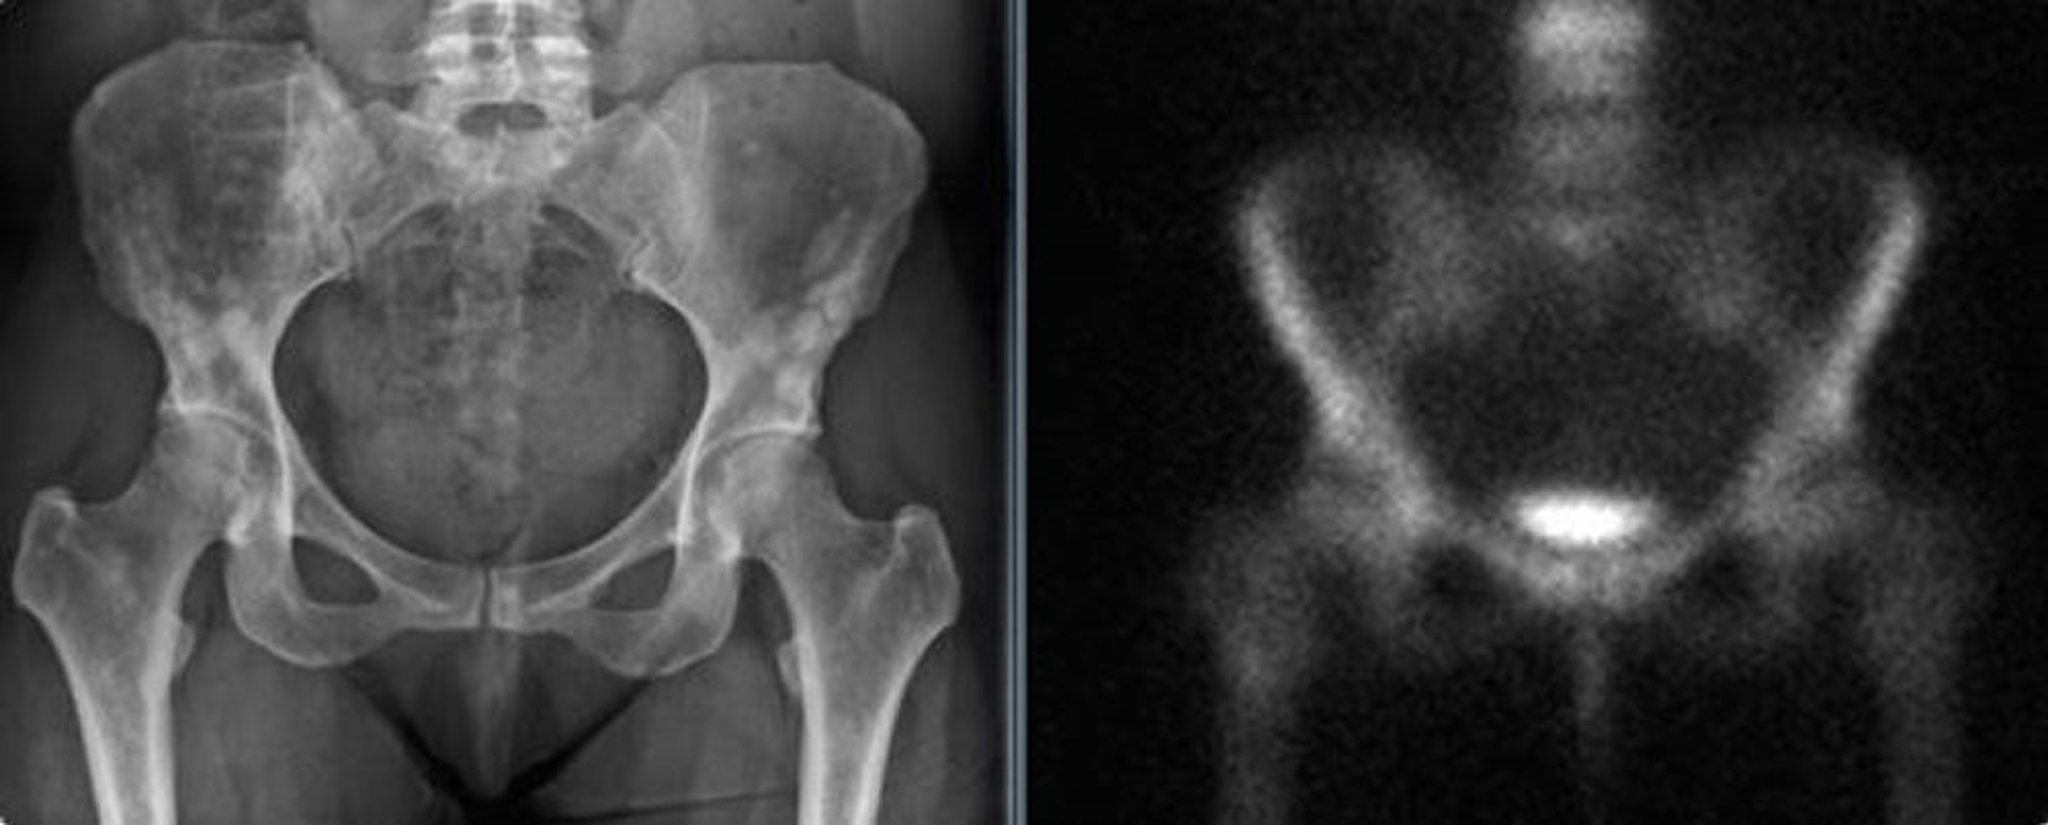

Ostéopoikilose du bassin

La radiographie pelvienne (à gauche) montre une ostéopoïkilose du bassin chez une femme adulte. Ces densités pourraient être confondues avec des métastases blastiques. La scintigraphie osseuse (à droite) ne montre pas d'augmentation significative de la captation.

Images courtesy of Michael J. Joyce, MD, and David M. Joyce, MD.